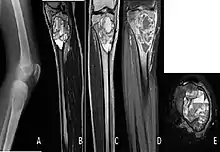

A. X-ray: osteolytic lesion in tibia near knee. B/C/D/E. MRI with E showing fluid levels. | |

X-ray and CT scan show lytic expansion lesions with clear borders.[1] Expansion of cortex gives the lesion a balloon-like appearance. Larger lesions may appear septated.[11] MRI reveals fluid levels.[1] Bone scan shows outer radiotracer uptake, with a central dark area.[1][11]